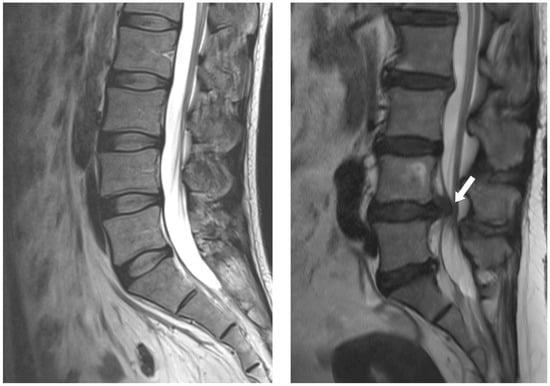

- Altun, I.; Yüksel, K.Z. Lumbar herniated disc: Spontaneous regression. Korean J. Pain. 2017, 30, 44–50. [Google Scholar] [CrossRef] [PubMed]